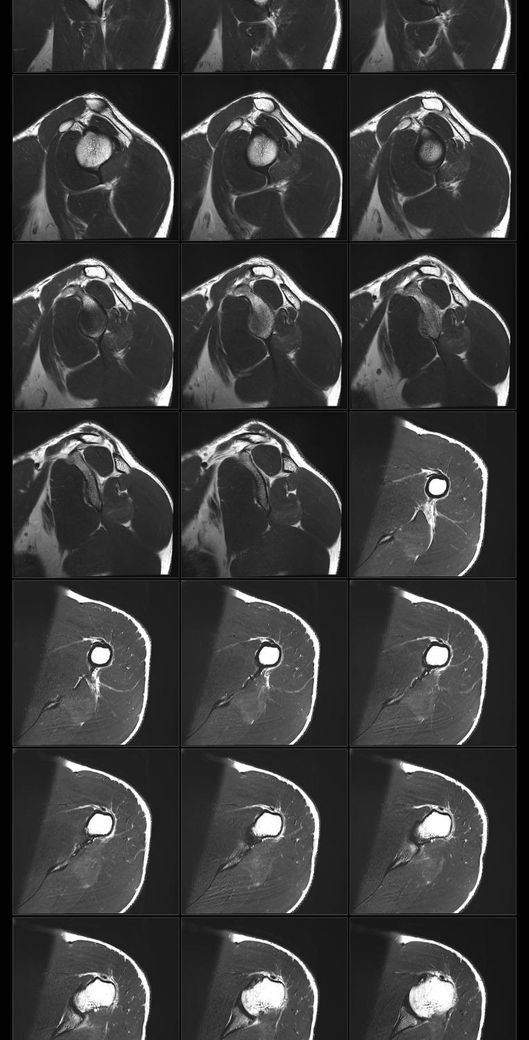

어깨 mri 전문의 소견 부탁드립니다

얼마전에 축구하다가 넘어지고 그날 저녁부터 팔이 안올라가서 건협가서 mri 찍었습니다.

회전근개 파열이 있는지, 없다면 지금 상태가 어떤상태인지와 웨이트 운동 가능할정도의 회복기간이 궁금합니다

• 1번 째 사진

• 2번 째 사진

• 3번 째 사진

• 4번 째 사진

• 5번 째 사진

• 6번 째 사진

• 7번 째 사진

• 8번 째 사진